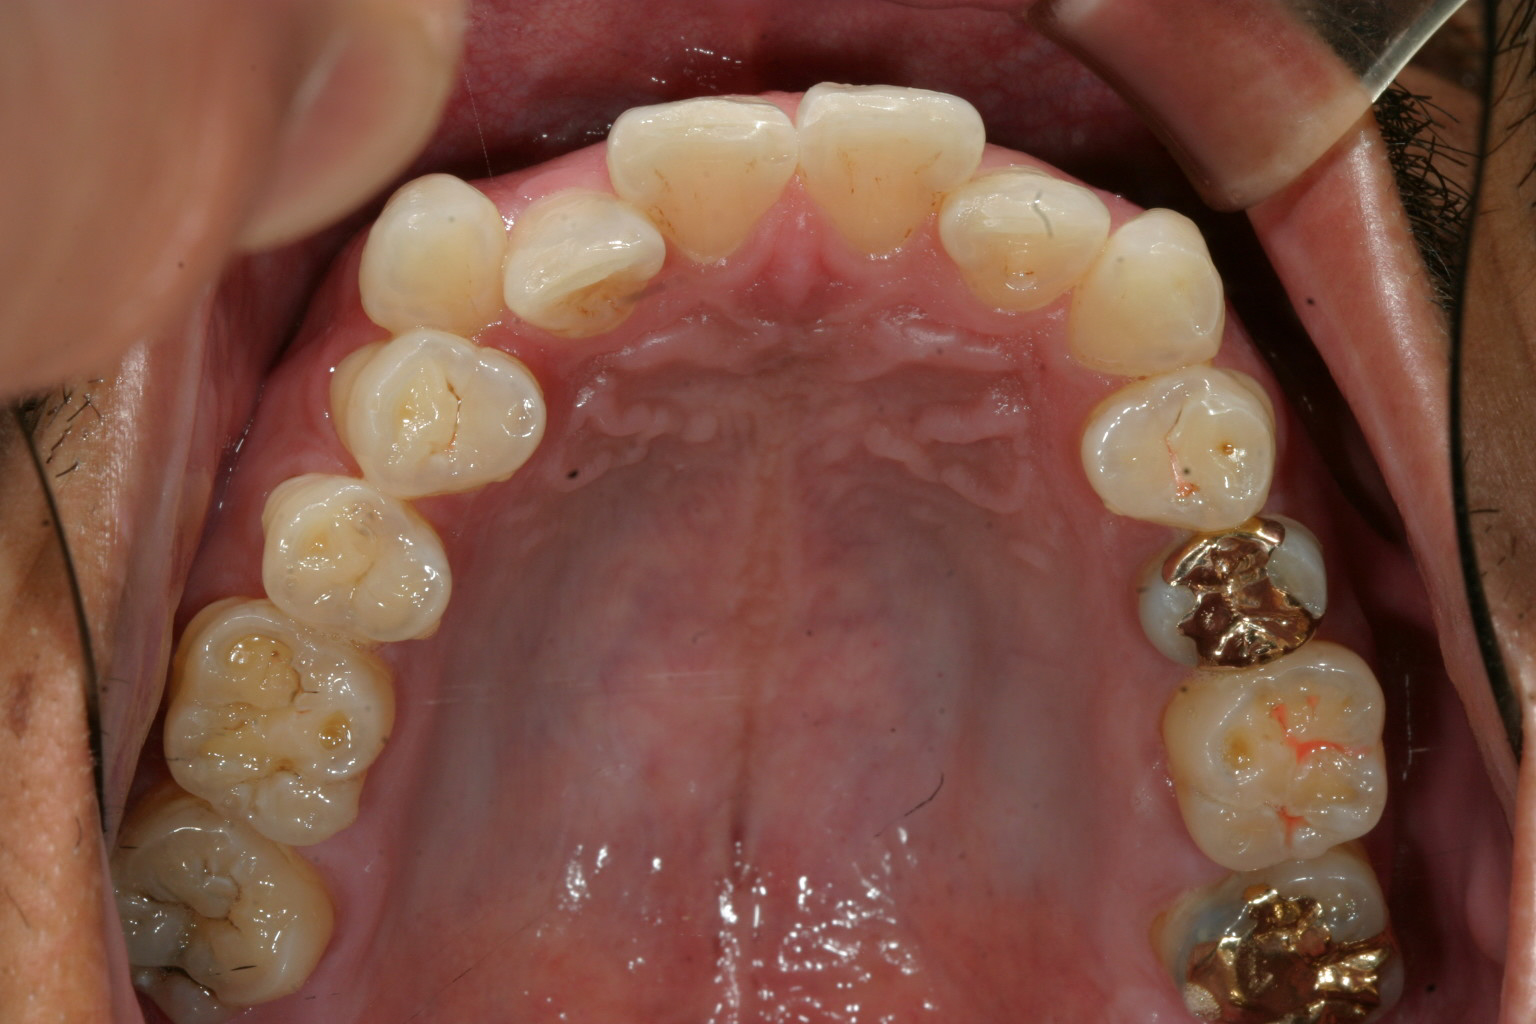

右の犬歯の突出が目立ちます。

インビザラインにて右側臼歯遠心移動(右側の大臼歯から順番に歯を後ろに下げて犬歯の入るスペースを確保する方法)